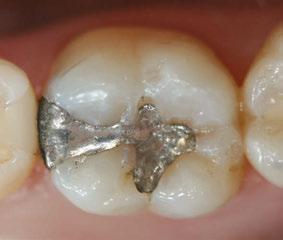

The 5-year-old patient featured in this case study did not benefit from early oral care and had multiple carious lesions. Considering the young age, high caries risk, and the uncertainty of compliance with follow-up appointments, I wanted to restore and seal all teeth in one visit. One quadrant is shown in this case study. The carious lesion on tooth J (65) was cavitated and prepared, restored, and sealed. Tooth I (64) was non-carious and would only be sealed (Figure 1).

I chose Activa™ Kids Bioactive-Restorative and Activa Presto (Pulpdent) as restorative materials for this case because I have seen excellent clinical results over time with these bioactive materials. Continuous release and recharge of calcium, fluoride, and phosphate from these restoratives are beneficial in the fight against decay long into the future.

Choosing restoratives based on ease of use and the ability to work quickly was important in this case. All restorations were completed under general anesthesia in one appointment. There were wear facets on the occlusal surfaces of the molars, so it was important to use a material that would have some flexibility and resistance to fracture. The innovative composition of Activa Kids includes an elastomeric monomer or “rubberized” component that absorbs forces and was an ideal filling material. Activa Presto shares similar properties, and it was convenient to use as an occlusal surface sealant for this patient.

Tooth J (65) was prepared with a coarse tapered high-speed diamond bur allowing for some minor mechanical retention by incorporating minimal undercut in preparation. The occlusal

surface of tooth I (64) was also lightly abraded with a diamond bur (Figure 2). The preparations were selectively etched with phosphoric acid, rinsed, and lightly dried (Figure 3). Bonding agent was applied to the entire occlusal surfaces of both teeth, air thinned, and light-cured (Figure 4).

Tooth J (65) was bulk-filled with Activa Kids. For this fast injection technique, I place the dispensing tip at the floor of the preparation and extrude the material without removing the tip until the preparation is completely filled (Figure 5). I like to do some minor manipulation of the filling material with hand instruments to create anatomy, as well as to ensure the material is flush with the surface of the preparation, and no air is trapped inside. Activa Kids is dual-cure, ideal for bulk filling, and can be cured with all lights. A thin topcoat of Activa Presto was placed as a sealant on the entire occlusal surface of teeth I and J (64 and 65) (Figure 6). Figure 7 shows the final clinical situation.

Figure 1 (left): Caries lesion on tooth J (65). Figure 2 (center): Preparation of tooth J (65) and abraded occlusal surface of tooth I (64). Figure 3 (right): Selective etch of enamel Figure 4 (left): Bonding agent is applied to both teeth I and J (64 and 65). Figure 5 (right): The preparation is filled with ACTIVA Kids Figure 6 (left): A thin topcoat of ACTIVA Presto is applied to the occlusal surfaces of teeth I and J (64, 65). Figure 7 (right): Final result